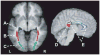

Multiple functional methods including functional magnetic resonance imaging, transcranial magnetic stimulation, and positron emission tomography have shown cortical reorganization in response to blindness. We investigated microanatomical correlates of this reorganization using diffusion tensor imaging and diffusion tensor tractography (DTT). Five early blind (EB) were compared with 7 normally sighted (NS) persons. DTT showed marked geniculocalcarine tract differences between EB and NS participants. All EB participants showed evidence of atrophy of the geniculocortical tracts. Connections between visual cortex and the orbital frontal and temporal cortices were relatively preserved in the EB group. Importantly, no additional tracts were found in any EB participant. Significant alterations of average diffusivity and relative anisotropy were found in the white matter (WM) of the occipital lobe in the EB group. These observations suggest that blindness leads to a reorganization of cerebral WM and plausibly support the hypothesis that visual cortex functionality in blindness is primarily mediated by corticocortical as opposed to thalamocortical connections.